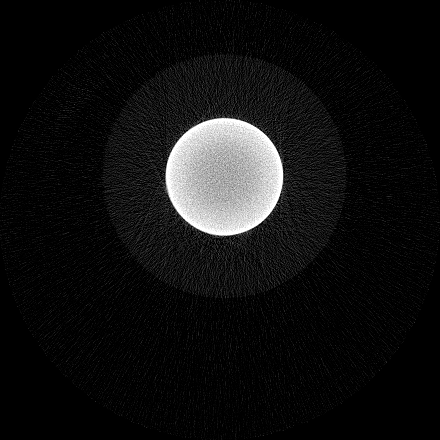

Figure 5 illustrates a single slice spectral reconstruction of the Ti scaffold. Varying levels of streak artefacts can be seen across the spectral reconstructions. The spectral reconstructions for the energy ranges 35 to 80 keV, 55 to 80 keV, and 62 to 80 keV shown in figure 5, exhibit reduced streak artefacts. A region-of-interest (ROI) analysis was performed in the immediate vicinity of the metal region where the streaks are more pronounced. Average attenuation coefficent of air close to zero conveys less regional noise/artefacts. The regional average attenuation coefficient (μROIsubscript𝜇𝑅𝑂𝐼\mu_{ROI}) of the non-metal (air) region in 55 to 80 keV reconstruction (figure 5c) shows reduced artefacts. Even though minor streaks and statistical noise appear in figure 5d due to photon limitation, the artefacts are less pronounced in comparison to the wide energy acquisition in figure 5a.

Refer to caption

(a) 15 to 80 keV

(b) 35 to 80 keV

(c) 55 to 80 keV

(d) 62 to 80 keV

Figure 5: Single slice spectral reconstruction of Ti scaffold sample. μROIsubscript𝜇𝑅𝑂𝐼\mu_{ROI} is 0.246, 0.030, 0.008 and 0.103 for the circular ROI in (a), (b), (c) and (d) respectively.